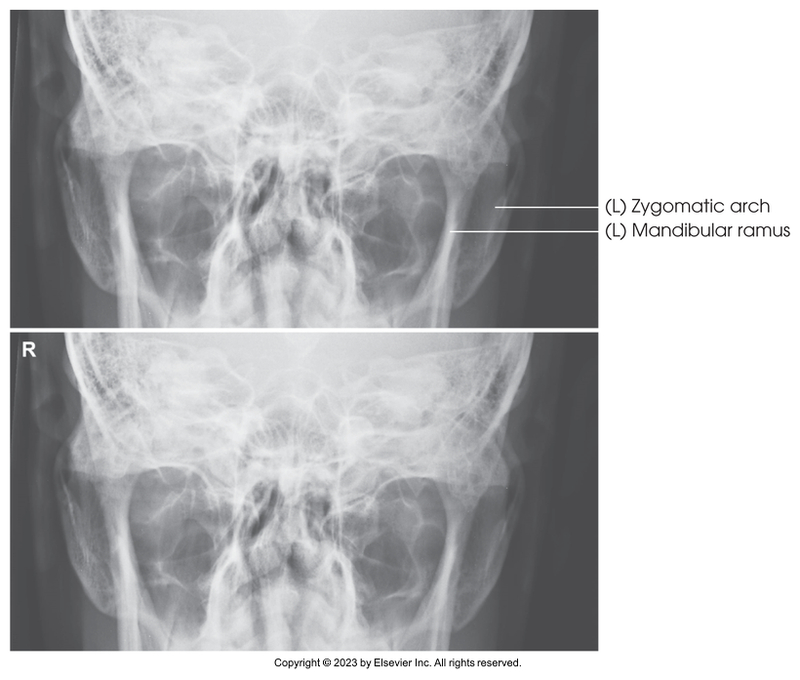

AP axial of the zygomatic arches - Modified Towne method

AP axial of zygomatic arches - Modified Towne method